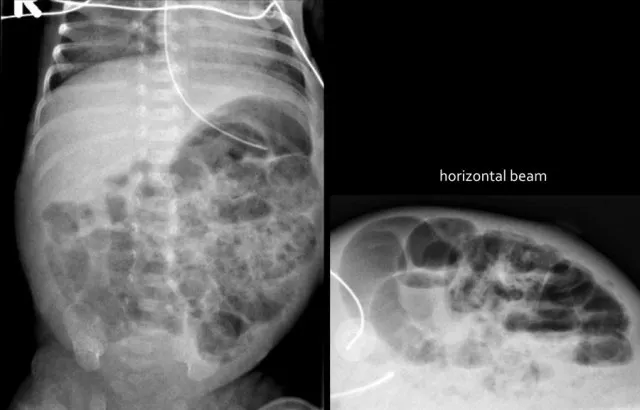

- Necrotizing Enterocolitis (NEC):

- X-ray: Pneumatosis intestinalis (hallmark), portal venous gas (ominous), pneumoperitoneum (perforation: Rigler"s, football signs).

- Bell"s Staging (I-III).

⭐ Portal venous gas in suspected NEC is ominous, indicating bowel necrosis and possible perforation.

- NEC: Pneumatosis intestinalis is pathognomonic; look for portal venous gas or free air (perforation).